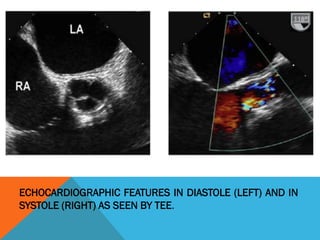

ECHOCARDIOGRAPHIC FEATURES IN DIASTOLE (LEFT)

AND IN SYSTOLE (RIGHT) AS SEEN BY TEE.

ECHOCARDIOGRAPHIC FEATURES IN DIASTOLE (LEFT) AND IN

SYSTOLE (RIGHT) AS SEEN BY TEE.